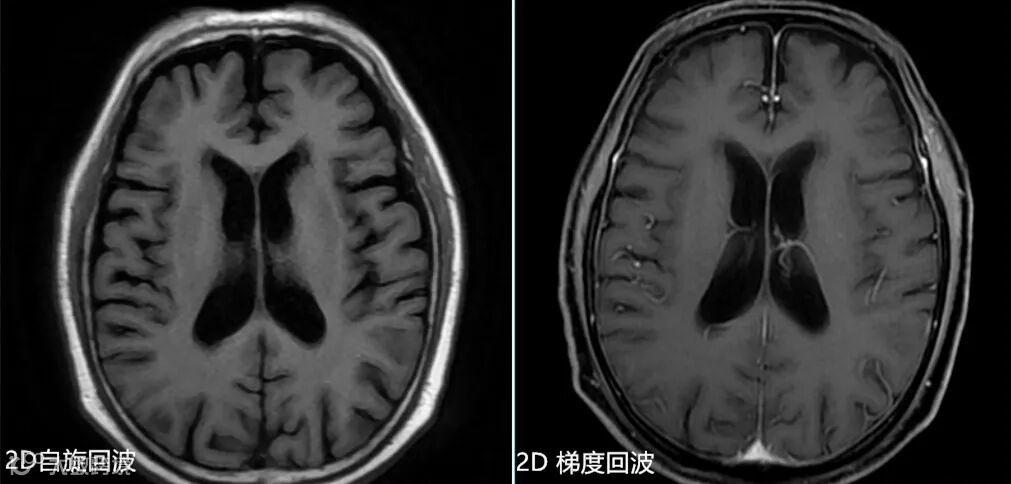

- 但该序列磁敏感伪影较重,图像灰白质对比也不及自旋回波序列,特别是采用压脂后其图像对比明显下降。如上图△,2D T1自旋回波序列与2D T1扰相梯度回波序列的比较。